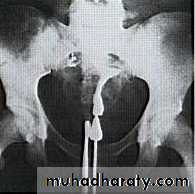

HSG outlining the uterine and tubal anatomy